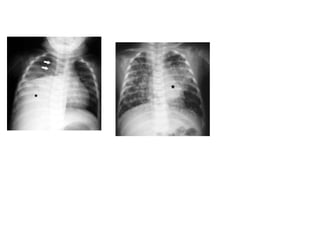

Radiological diagnosis

Chest X-ray

CXR remains an important tool for diagnosis of PTB in children who are sputum smear

negative or who cannot produce sputum

The following abnormalities on CXR are suggestive of Tb :-

• Enlarged hilar lymph nodes and opacification in the lung tissue.

• Miliary mottling in lung tissue

• Cavitation (tends to occur in older children)

• Pleural or pericardial effusion – though seen on CXR – are forms of extra

pulmonary TB that tend to occur in older children

• The finding of marked abnormality on CXR in a child with no signs of respiratory

distress (no fast breathing or chest indrawing) is supportive of TB

Primary Tuberculosis on CXR

1.GangliopulmonaryTB ( Characterized by the presence of

mediastinal and/ or hilar lymphadenopathy and

parenchymal abnormalities, the Ghonfocus

2.TuberculousPleuritis

3.MiliaryTB

4.Tracheobronchial TB

Radiological diagnosis Chest X-ray CXRremains an important tool for diagnosis of PTB in children who are sputum smear negative or who cannot produce sputum The following abnormalities on CXR are suggestive of Tb :- • Enlarged hilar lymph nodes and opacification in the lung tissue. • Miliary mottling in lung tissue • Cavitation (tends to occur in older children) • Pleural or pericardial effusion – though seen on CXR – are forms of extra pulmonary TB that tend to occur in older children • The finding of marked abnormality on CXR in a child with no signs of respiratory distress (no fast breathing or chest indrawing) is supportive of TB

Primary Tuberculosis onCXR 1.GangliopulmonaryTB ( Characterized by the presence of mediastinal and/ or hilar lymphadenopathy and parenchymal abnormalities, the Ghonfocus 2.TuberculousPleuritis 3.MiliaryTB 4.Tracheobronchial TB